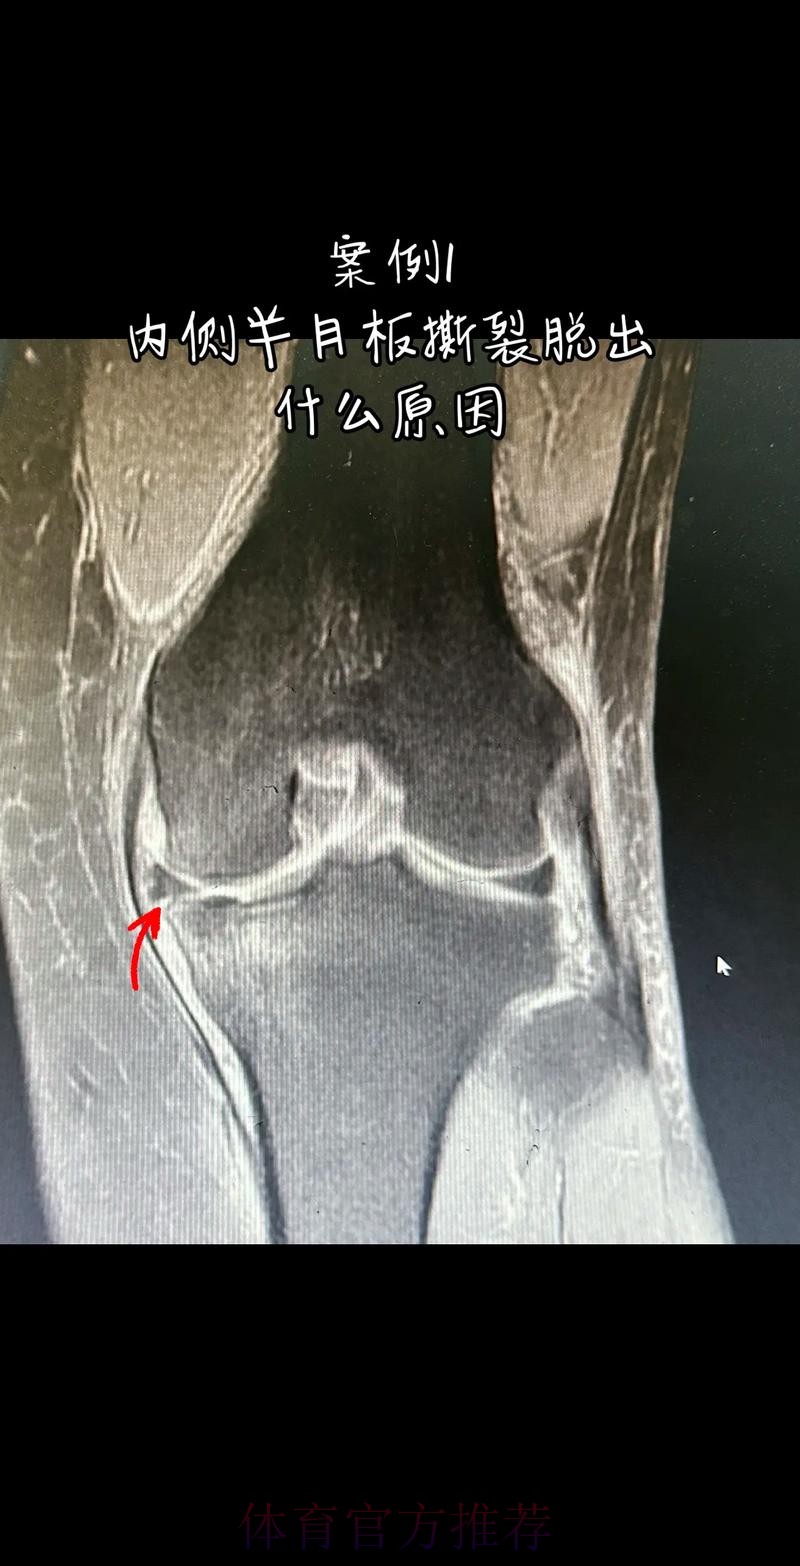

从医学角度看 半月板是膝关节内一块呈“C”形的软骨结构 其作用是缓冲冲击 稳定膝关节 并帮助分散压力 “左膝内侧半月板撕裂”通常说明在一次急停 旋转 或对抗中 半月板受到了超过其承受极限的力导致结构损伤 这类伤病常见于足球 篮球等需要频繁变向和对抗的项目 对于职业球员而言 半月板损伤严重程度不一 但共同点是都会影响支撑发力 跳跃以及变向时的稳定性 而官方给出的“预计伤缺6-8周”这个时间区间 往往对应的是中度损伤或通过微创手术加积极康复能够较快回归的情况 也意味着暂时没有出现必须长时间休战的最坏结果

表面上看 6-8周只是一个时间区间 但对顶级球队的赛程来说 这段时间可能包含多场联赛 甚至关键杯赛淘汰轮 相当于缺席一个赛季中最密集的一段周期 需要强调的是 这个“预计”并不是绝对数字 它取决于撕裂的位置 大小 修复方式 以及球员个体的恢复能力 有时若采取保守治疗 球员在6周时即可参与部分训练 但要达到比赛要求则可能接近8周甚至稍长 此外 精英运动员的康复不仅仅是伤口愈合 还包括力量恢复 协调重建 和心理自信的回归 阿拉巴要在有限时间内完成从“伤病患者”到“可靠首发”的角色转换 这一过程复杂程度远远超出一纸通告所能呈现

在“官方 预计伤缺6-8周”这段时间里 阿拉巴需要完成的康复目标可以概括为三个层面 首先是生理层面 半月板区域的疼痛与炎症控制 关节活动度的恢复 以及周围肌群力量的增强 其中股四头肌 腘绳肌与臀部肌群的力量对膝关节稳定至关重要 其次是功能层面 需要通过特定训练重新建立变向 跳跃 对抗中的信心 包括在接近比赛速度下的模拟对抗训练 最后是心理层面 对于一名习惯于每三天一战的球员 突然被迫远离比赛容易产生焦虑和不安 这时教练团队 家人和队友的支持就显得尤为重要 若这三个层面协调推进 他在伤缺期结束后能更自然地融入比赛节奏